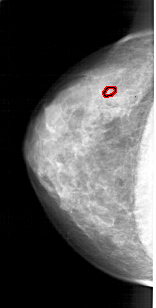

A_1914_1.LEFT_MLO

LEFT_MLO LINES 5326 PIXELS_PER_LINE 2446 BITS_PER_PIXEL 12 RESOLUTION 43.5 OVERLAY

FILE: A_1914_1.LEFT_MLO.OVERLAY

TOTAL_ABNORMALITIES 1

ABNORMALITY 1

LESION_TYPE CALCIFICATION TYPE PLEOMORPHIC DISTRIBUTION CLUSTERED

ASSESSMENT 4

SUBTLETY 2

PATHOLOGY BENIGN

TOTAL_OUTLINES 1

BOUNDARY